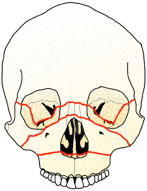

上の絵は、骨折の良く起きる場所です。